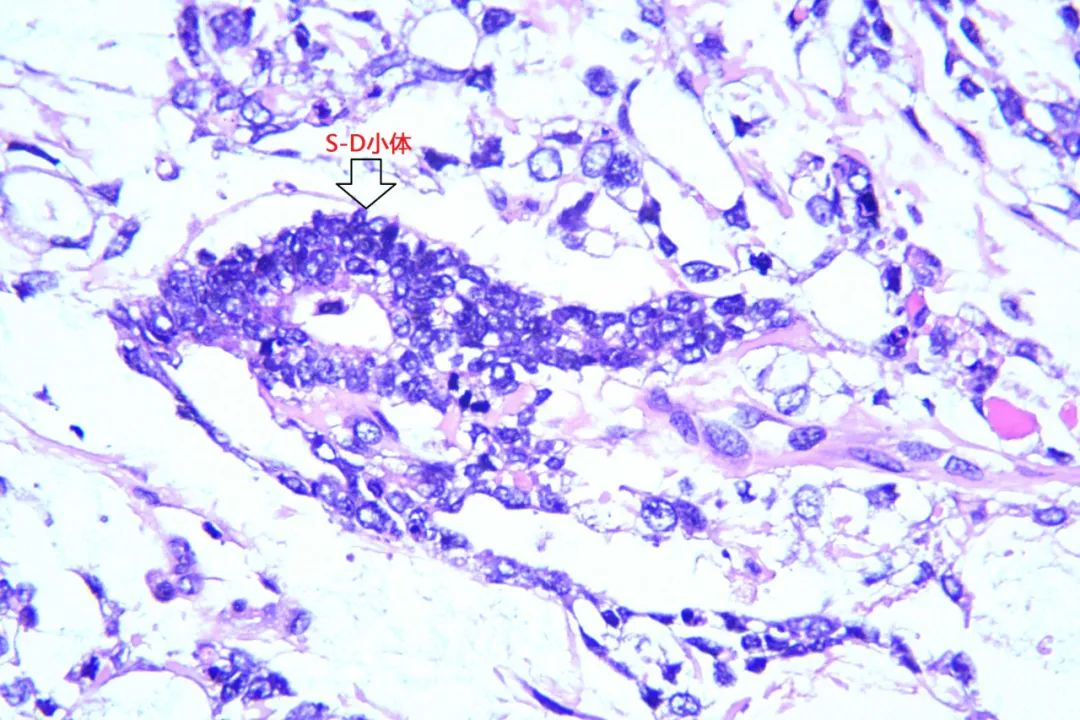

小颜在家人的陪同下来到我院妇科诊治,此时的小颜腹部已如孕6+月大小。住院后小颜莫名出现反复发热,抗感染治疗数日疗效欠佳。妇科主任米建锋经过系统全面的检查,考虑小颜的盆腹腔巨大肿物为卵巢恶性肿瘤的可能性极大,且发热考虑由该巨大肿瘤引起,建议尽快进行手术治疗。经与小颜家属沟通病情后决定行保留生育功能的手术治疗。术中发现巨大肿物来源于左侧卵巢,大小约25cm×20cm×12cm,包块与大网膜致密粘连,表面出血,腹腔内大量淡黄色积液约1500ml。在米建锋及普外科逄世江副主任医师的通力合作下,完整将小颜体内重二十余斤的肿物切除。米建锋表示,卵巢卵黄囊瘤又称内胚窦瘤,是一种原始生殖细胞肿瘤,恶性程度高,约占恶性卵巢生殖细胞肿瘤的20%,发病率仅次于无性细胞瘤,常见于儿童及育龄期女性,也有妊娠期发现。临床上由于肿瘤增长快,体积较大,又易有包膜破裂及腹腔内种植,往往起病急。腹痛是本病最常见的症状,肿瘤坏死、出血可使体温升高而有发热症状。首选的治疗方案为手术联合化疗,该肿瘤恶性程度高,但对化疗较敏感,手术恢复后可通过有效的联合化疗来延缓疾病的复发。